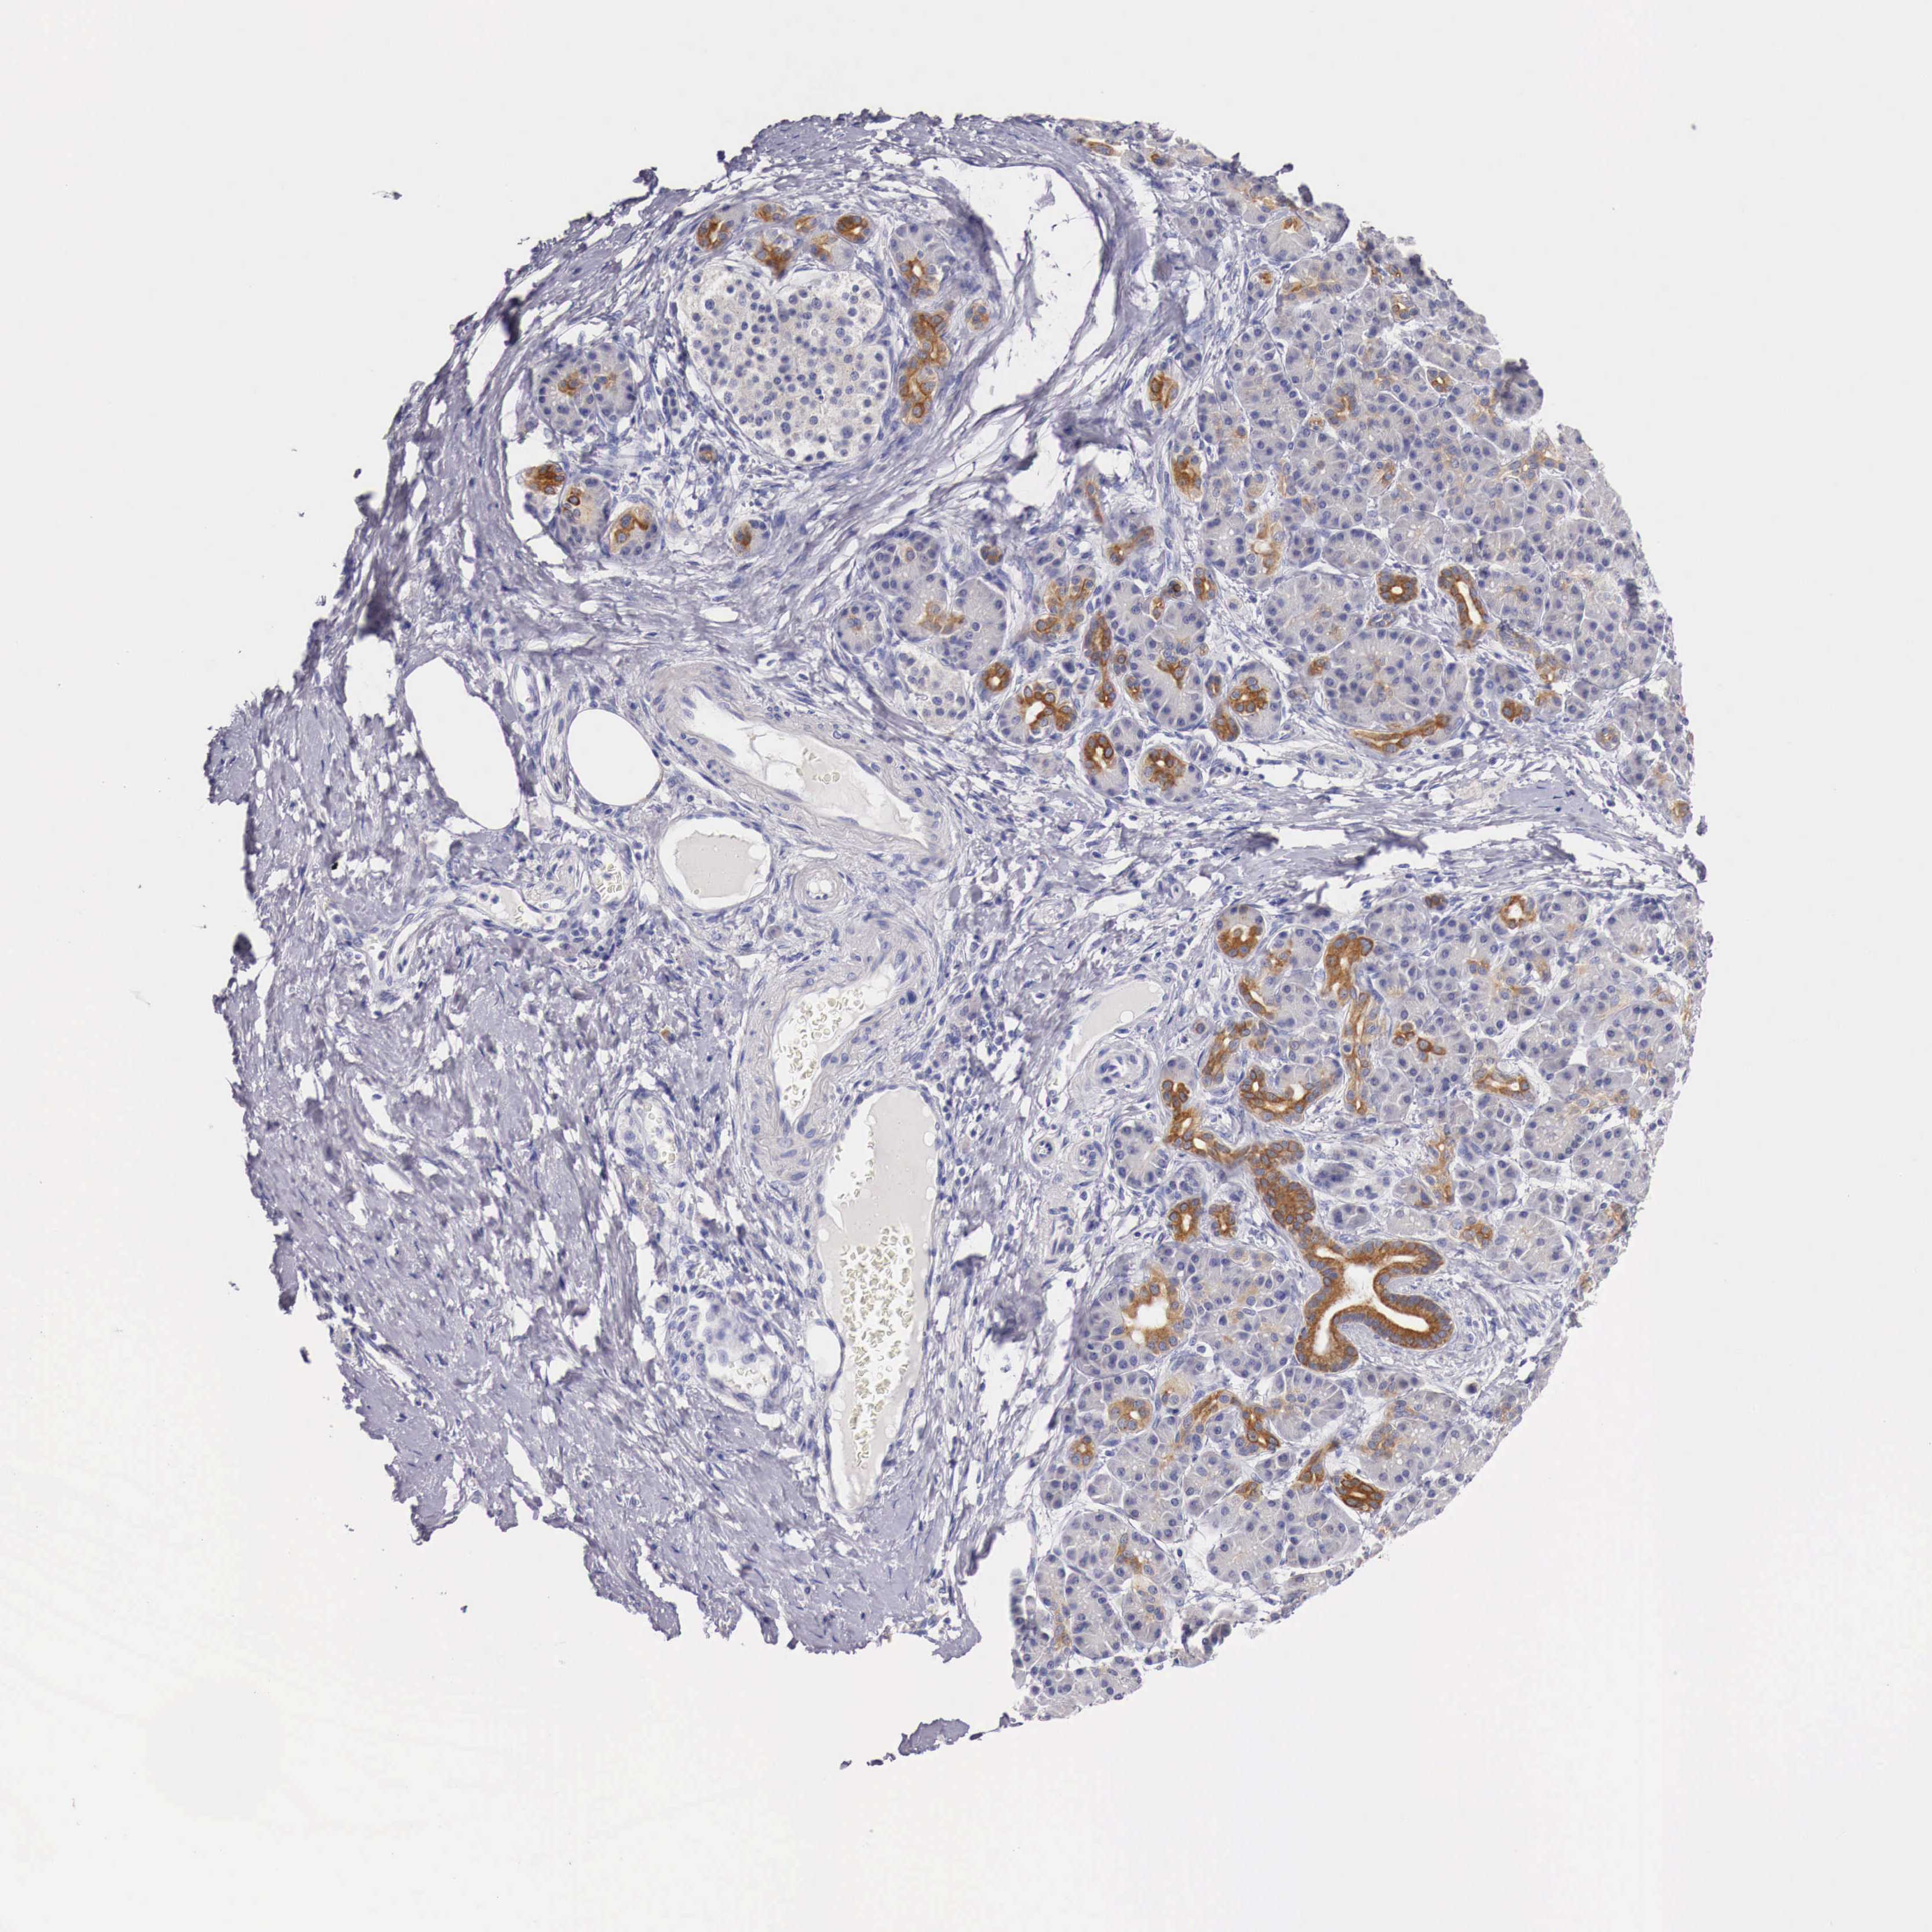

PANCREATIC CANCER - Protein expressioni

A mouse-over function shows sample information and annotation data. Click on an image to view it in a full screen mode. Samples can be filtered based on level of antibody staining by selecting one or several of the following categories: high, medium, low and not detected. The assay and annotation is described here.

Note that samples used for immunohistochemistry by the Human Protein Atlas do not correspond to samples in the TCGA dataset.

Antibody stainingi

Antibody staining in the annotated cell types in the current human tissue is reported as not detected, low, medium, or high, based on conventional immunohistochemistry profiling in selected tissues. This score is based on the combination of the staining intensity and fraction of stained cells.

Each image is clickable and will lead to virtual microscopy that enables deeper exploration of all samples and also displays staining intensity scores, fraction scores and subcellular localization as well as patient and tissue information for each sample.

Antibody HPA000545

Staining

High

Medium

Low

Not detected

Intensity

Strong

Moderate

Weak

Negative

Quantity

>75%

75%-25%

<25%

None

Location

Nuclear

Cytoplasmic/membranous

Cytoplasmic/membranous,nuclear

Adenocarcinoma, NOS